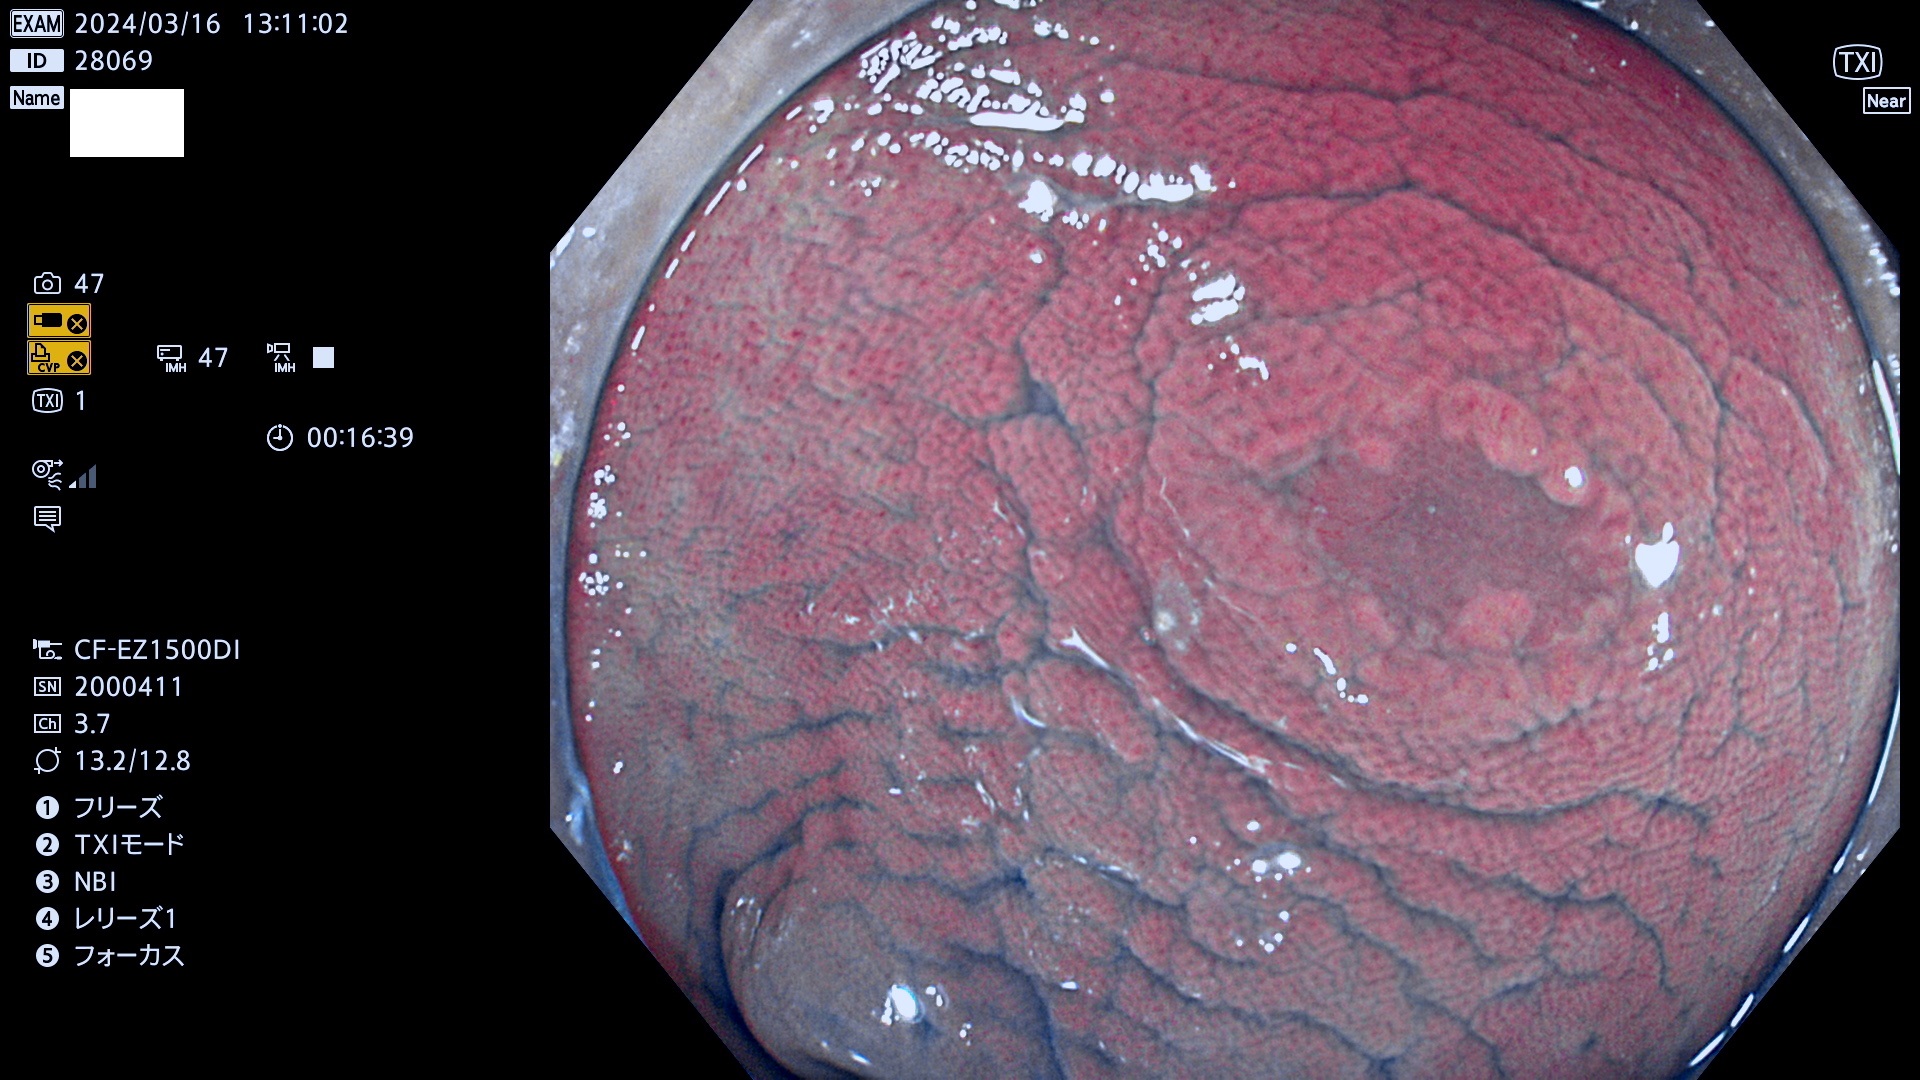

表面型腺腫(Flat Adenoma)の中で、完全に平坦な物をUb、陥凹している物をUcと呼びます。平坦隆起型(Ua)よりも、発見が難しく危険な病変です。

ビランと鑑別の困難な腺腫